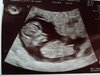

A o 15.00 byłam na wizycie, Pchełka ma 4.26 cm, serducho 168 uderzeń na minutę, fikanie raczkami i nózkami też zaliczone podczas badania :)

A oto i ta Pchła!! [emoji7]

A oto i ta Pchła!! [emoji7]Zobacz załącznik 916854

Super, ze wszystko sie udalo :) Dzidziuś już taki wyraźny :)